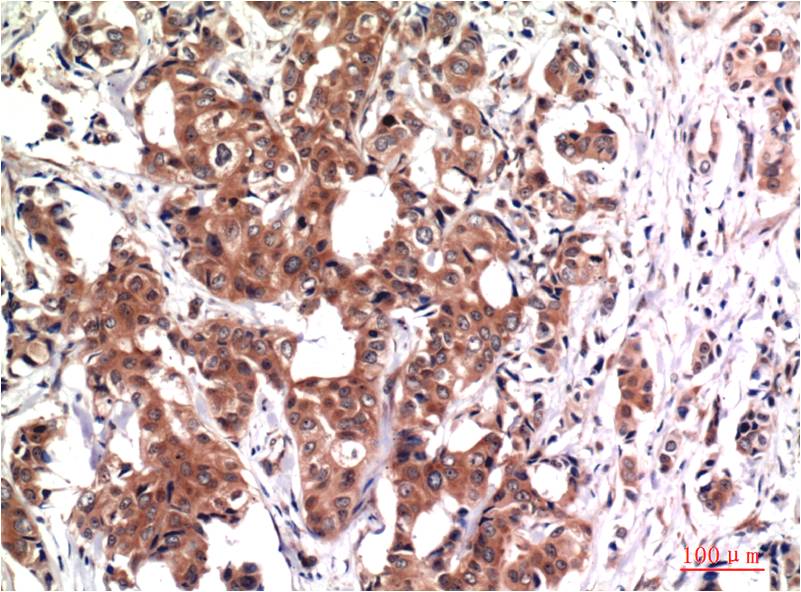

WB, IHC

Human, Rat, Mouse

WB 1:1,000-2,000 IHC 1:100-200